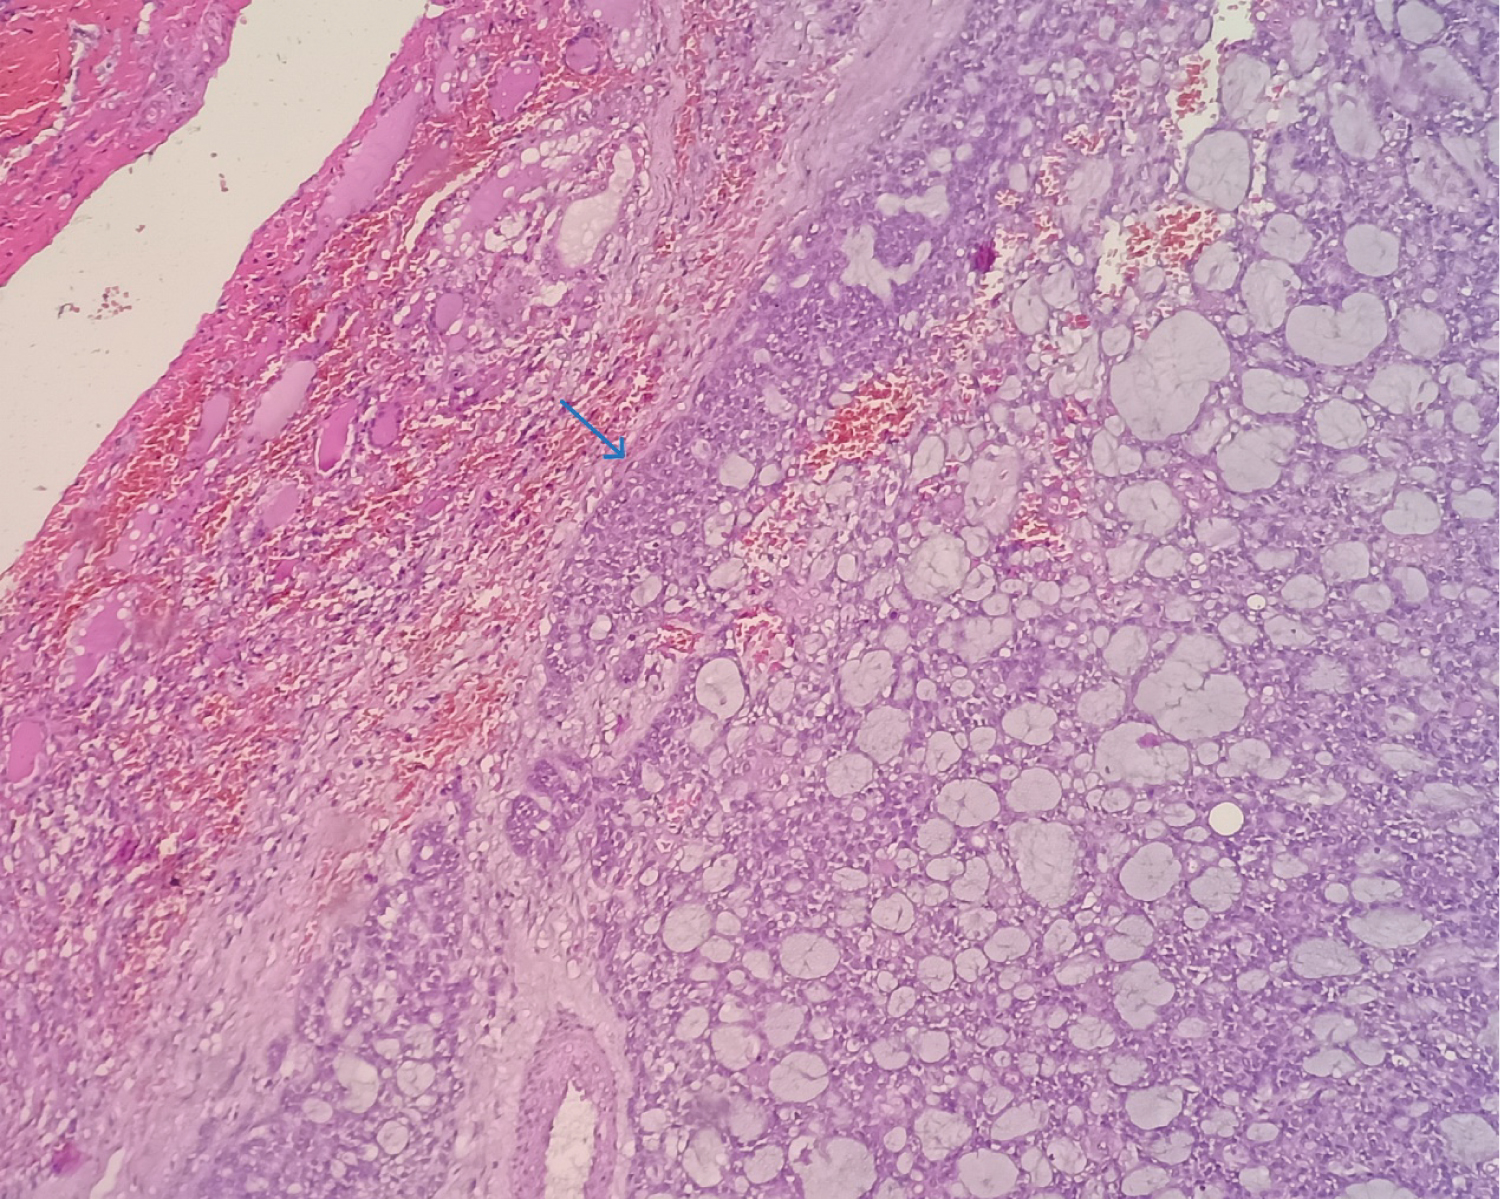

A 38-year-old female presented with the complaints of pain and difficulty during swallowing and history of weight loss. Up on examination, a swelling was noted on the left side of her neck, which moved with deglutition. Ultrasound (USG) revealed a well circumscribed hypo echoic nodule measuring 3.2 × 2.1 cm in the left lobe of thyroid with no extrathyroidal extension, however the nodule was compressing the esophagus. Fine needle aspiration was performed on the lesion and stained with Papanicolaou (PAP) stain and May Grunwald Geimsa (MGG) stains. The smears exhibited high cellularity with globoid clusters and three dimensional tissue fragments composed of aggregates of cells with central core of homogenous basement membrane material with cells having basaloid morphology and scant cytoplasm (Figure 1). MGG smears highlighted pink/ magenta amorphous basement membrane hyaline globules in the clusters of tumor cells (Figure 2). Cell block preparation of fine needle aspiration showed cribriform pattern of tumor cells with hyaline globules (Figure 3). Immunocytochemistry conducted on cell block shows TTF-1 positivity in normal thyroid follicles and negative staining in tumor cell clusters. CD117 and synaptophysin were inconclusive on cell block, but based on morphology this case was reported as adenoid cystic carcinoma of thyroid. Contrast-enhanced computed tomography (CECT) prior to surgery depicted a well defined heterogeneously enhancing hypodense lesion in the left lobe of thyroid measuring 3.2 × 2.1 × 1.7 cm with no additional lesions or abnormalities noted in the adjacent structures like trachea, larynx, oesophagus or upper mediastinum (Figure 4). The excised left hemi-thyroidectomy specimen was received which showed a grey white solid homogenous lesion measuring 3.5 × 2.2 × 2 cm reaching till the capsule. No cystic spaces/papillary projections/colloid seen in the lesion grossly. Adjacent thyroid parenchyma was normal. Histopathology sections showed tumor arranged in tubules and cribriform pattern along with hyaline globules suggesting the diagnosis of adenoid cystic carcinoma of thyroid, limited to thyroid without extrathyroid extension (Figure 5). IHC with CD117 showed cytoplasmic positivity in tumor cells further supporting the diagnosis (Figure 6).

Figure 5: H&E section from Left hemi thyroidectomy specimen (20x) show well circumscribed tumor with features of adenoid cystic carcinoma, limited to thyroid with adjacent normal thyroid parenchyma (Arrow marks the junction of tumor with normal thyroid parenchyma). View Figure 5